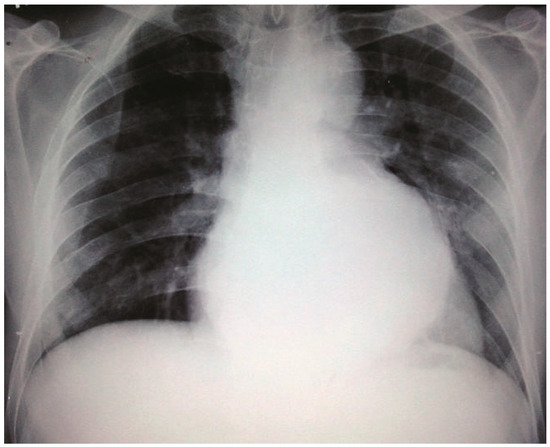

Neo Snowman in X-Ray

Case report